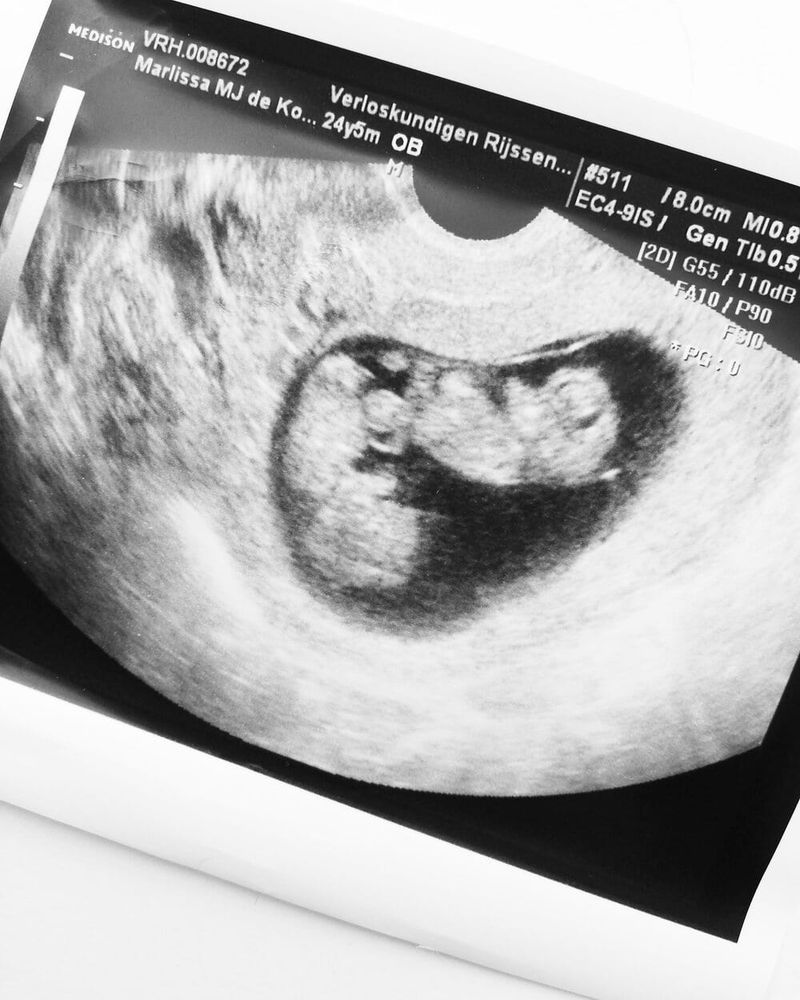

Daniel: Toen we in de kamer waren bij de verloskundige ging het heel snel, gelukkig maar want met twee van die jongens moest het zeker niet te lang duren. Ze begon met de echo en toen was het stil… Er gaat dan van alles door je hoofd. Klopt het hartje wel? Zit het vruchtje op de goede plek? Uiteindelijk kwamen de woorden: ‘Ik zie hier een hartje kloppen, en ik zie er hier één’. Ze zag gelijk dat het om een eeneiige tweeling ging. Maar toen kwam de grote vraag. Zit er wel of geen vlies tussen de meisjes? Met een uitwendige echo kon ze dit slecht zien, dus kreeg Marlissa een inwendige echo. Na een best lange zoektocht kon ze heel lichtjes een vlies zien. Gelukkig! Wat een opluchting.

Marlissa: Eenmaal thuisgekomen werd Google afgestruind naar de meest schattige foto’s van eeneiige tweelingen. Wat was dit bijzonder. Niet één, maar twee kindjes groeiden in mijn buik. Het weekend hierna gingen we naar onze ouders om ons nieuwtje te vertellen. Ik was best zenuwachtig, want hoe gaan ze hierop reageren? We hadden namelijk al twee jongens van toen 1 en 2 jaar, en dat was al heel wat. Helemaal als er straks een oppas nodig zou zijn of we iets zouden hebben met familie, hoe zou dat dan moeten. Gelukkig reageerden onze families heel leuk en vonden ze het heel bijzonder. Achteraf gezien hadden we dat ook wel kunnen verwachten. Ik maakte me veel te druk. Onze eerste afspraak bij de gynaecoloog was allesbehalve fijn. Waar we toch een beetje bang voor waren, was zo. Hij zag geen tussenvlies. Oftewel een mono mono tweeling. Heftig, heel heftig vonden we dit. We hadden een gesprek over de risico’s en wat er allemaal mis kon gaan. We stonden gelijk weer met beide benen op de grond. We gingen een hele spannende zwangerschap tegemoet. Want wat houdt een monochoriale-monoamniotische (monomono) tweeling in? De kindjes delen alles. Ze delen de placenta en ze delen de vruchtzak. Het grootste risico is dat de navelstrengen om elkaars nekje kunnen gaan zitten en hierdoor één of allebei kunnen overlijden. En een ander groot risico is dat de één meer voeding kan nemen waardoor de ander minder krijgt en ze dus uit balans raken waardoor de één heel hard groeit en de ander juist niet (door de gedeelde placenta).

Marlissa: Vanaf 20 weken kregen we om de week een echo en controle. En elke afspraak was weer spannend. Je voelt elke dag de kindjes bewegen, maar toch was het spannend. Het kon zo voorbij zijn. Ik voelde mij een tikkende tijdbom. Later kregen we elke week een echo. Eén keer in de zoveel tijd hadden we controles in het academisch ziekenhuis in Utrecht. Als de meisjes voor de 32 weken geboren zouden worden, moest ik hier bevallen. Was het na de 32 weken kon dit in ons eigen ziekenhuis in Deventer.

Daniël: Verbazingwekkend zag het er bij elke echo heel goed uit. Ze groeiden keurig net als een eenling. Elke goede en fijne uitslag probeerden we ook te vieren. Even een lekkere lunch of borrel (voor mij dan) ergens in de buurt van Deventer of Utrecht.